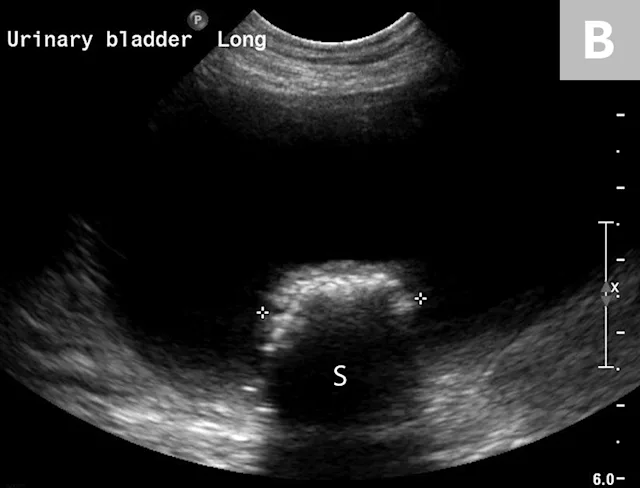

Clinical signs associated with ureteral calculi may range from chronic non-specific signs to acute or chronic renal failure. The presence of hydronephrosis can be highly suggestive of a ureteral obstruction (Figure 6).

FIGURE 6A

Mild to moderate right hydronephrosis and proximal ureteral dilation in a Dalmatian.